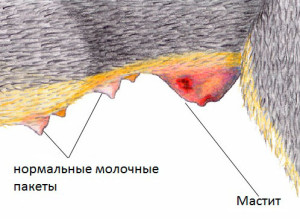

Мастит, как причина набухания сосков у кошек

Мастит– это инфекция или воспаление молочной железы, происходящие у кормящих кошек. Сопровожд

Застой в молочных железах, как причина набухания сосков у кошек

Застой в молочных железах – аномально большое количество молока в молочных железах. Причины, как правило, кроются в здоровье кошки. Первоначальный мастит (см. выше ) и другие болезни тяжело родившей кошки, отказ от кормления потомства и преждевременный отъём потомства от кормящей кошки – причина застоя молока в железах.